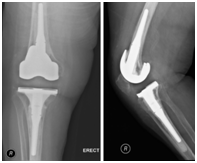

During the first-stage operation, the old prosthesis was removed and a spacer, which was filled with antibiotics, was inserted in its place. Intraoperative specimens were obtained from wound margins and sent for culture and histopathology. The results were positive for Brucella species.

The patient was started on antibiotic treatment with doxycycline for six months plus rifampicin and streptomycin for three weeks. After two months, the patient had a second-stage total knee replacement (Figure 2). After surgery, she was discharged on streptomycin and rifampicin. In her three-year follow-up, the patient was doing fine, she had a full 0 degree of right knee extension and 100 degrees of flexion, walks with a cane as a baseline after her spine surgery, and had no signs of prosthetic failure (Figure 3).